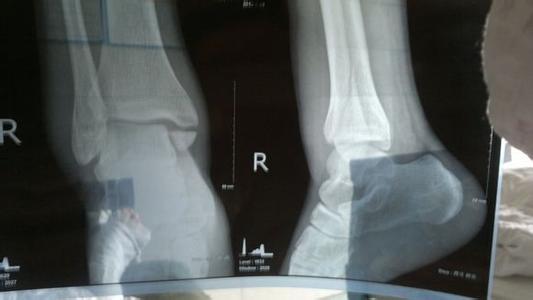

在遭遇到撕脱性骨折时(受伤部位通常会快速充血肿胀,疼痛感强),此时不要再移动受伤部位(多发生于脚踝,膝盖、肘关节部位),迅速到医院就诊于急诊科和外科、放射科检查治疗。